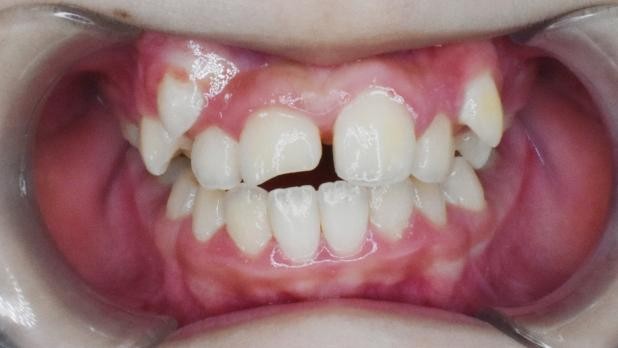

患儿的面像、口内情况如图所示。

可以看到患儿的下巴是偏斜的,面部不对称。经检查发现患儿口内可见多颗乳磨牙龋坏,有偏侧咀嚼习惯,存在颌骨发育的不对称。这种严重的骨性畸形需要双期矫治。第一期早期矫治,其目的是去除病因及干扰因素,让上下颌骨的生长导向正常,从矢状向、横向、垂直向去改善上下颌骨的不调。该患儿首先应用的是矫形力矫治器(螺旋扩弓器),协调上下颌骨宽度,去除锁合侧咬合干扰,建立双侧后牙咬合,治疗乳磨牙龋坏,同时指导患儿用双侧咀嚼食物促进咀嚼肌平衡发育。然后应用的是FRⅢ功能矫治器,解除前牙反合改善下颌偏斜,FRⅢ的作用原理是去除导致颌骨畸形的功能因素而且可以改善轻度的骨性错合。

下图为早期矫治前后面型和口内像对比,可以看到矫治后的患儿面型左右基本对称,下牙列的偏斜程度也明显改善,前牙的反合得到解除,去除了上颌骨发育的不利因素。接下来就是等待患儿换完牙以后进行二期治疗,二期治疗可以从三维方向上控制牙齿的移动方向,进一步平衡咬合,使得矫治效果更加稳定。二期治疗的矫治器可以选择固定矫治器也可以选择无托槽隐形矫治器。